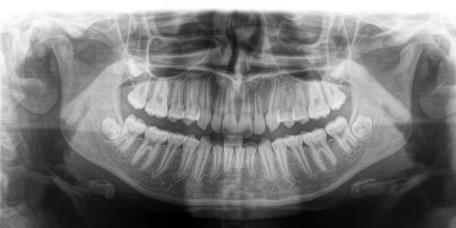

Et d’un appareil Carestream de radiographie permettant la réalisation de radiographie panoramique de type 2D, pour obtenir une vue globale de votre bouche à fin de mettre en place un diagnostic global

Et aussi des radiographies de type 3D, par Cone Beam ou Scanner dentaire, pour traitement Implantaire, exploration de dents de sagesses et analyse plus precise de foyers infectieux dentaire.